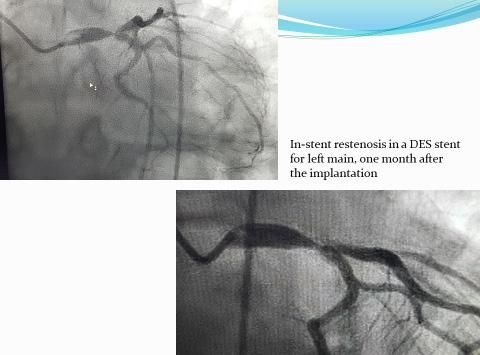

Coronary artery bypass grafting for in-stent restenosis

In the era of stenting, percutaneous coronary interventions are used as initial revas cularization strategy but there is the risk of in-stent restenosis in a significant number of cases. In-stent restenosis is an important clinical problem and those patients are a challenging group for both interventional cardiologists and cardiac surgeons as generally they are patients with aggressive coronary atherosclerosis in whom the recurrence of stenosis in case of percutaneous approach is probable to happen.

In-stent restenosis is mainly caused by intimal hyperplasia and sometimes by stent elastic recoil. There is consistent evidence that the percutaneous retre atment of these cases leads to suboptimal clinical results and is associated with high risk of additional restenosis or occlusion.

Coronary endarterectomy and stent removal

Because of the increasing use of mul tiple stents in diffuse and distal lesions of coronary arteries, the surgeon should use special and difficult techniques in order to perform coronary revascularization. One of them is coronary endarterectomy (CE) and stent removal followed by arte rial or venous grafting.

CE was first described by Bailey in 1957. It is performed in limited cases of diffuse and distal lesions. Livesay and Goldstein reported negative evidences in the ’90 that CE was associated with a high perioperative risk and poorer log term results but recent re ports changes this statement and shows safety and efficacy of CE and bypass grafting.

dered a contraindication for CABG. The extraction of stents and bypass grafting in selected cases is feasible with acceptable mortality and morbidity rates.

Coronary artery bypass grafting (CABG)

The profile of patients referred for CABG is continuously changing. The pa tients are older, the coronary lesions are more complex and there are more asso ciated co morbidities such as diabetes mellitus, hypertension, peripheral vascu lar disease, cerebral vascular disease. The patients are referred for surgery after one or more catheter based revascularization procedures thus with advanced stage and diffuse coronary artery disease.

Still optimal management of in-stent restenosis is controversial, but surgical approach seems to be a good alternative.

There are just a few articles and case reports on the surgical removal of pre viously implanted stents and subsequent bypass grafting.

Fukui in Japan reported in his 3 years series 11 consecutive patients with an giographically severe ISR treated with CE and stent removal concomitant with multivessel CABG In the presence of one or more stents within the anastomotic coronary segment should not be consi